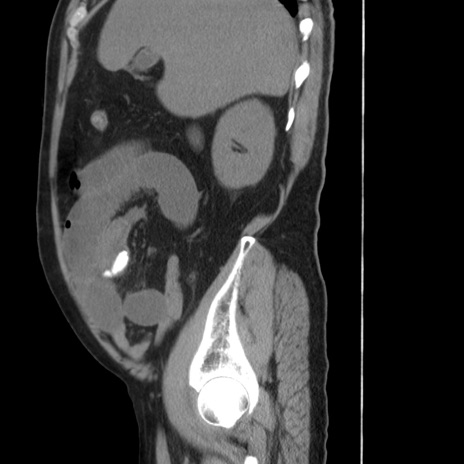

症例20(矢状断像)

【症例】 60歳代男性

【主訴】 腹部膨満、嘔吐

【現病歴】5日前頃より倦怠感を認め食事量減少し4日前の朝嘔吐、食事摂取困難となった。 3日前近医受診し点滴施行され整腸剤などを処方された。 当日他院を受診し、腹部膨満著明、炎症反応の上昇(CRP10.8、WBC11200)あり、紹介受診となる。

【身体所見】 意識JCS1 受け答えがはっきりしないBP 111/57mHg、 P 67bpm、、BT35.2°C、SpO2 97%(RA)、 腹部:膨隆、打診で鼓音あり、全体的に圧痛有り、腸蠕動音(-)、反跳痛ははっきりせず。

【データ】WBC 11400、CRP 14.20